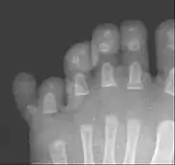

پُرانگشتی یا پلیداکتیلی (به انگلیسی: Polydactyly) نوعی بیماری مادرزادی است که در آن فرد بیمار بیش از پنج انگشت در هر دست یا پا دارد. این بیماری از شایعترین بیماریهای مادرزادی است. به طور میانگین در هر ۵۰۰ نوزاد متولد شده٫ ۱ نوزاد مبتلا به پلی داکتیلی است. پلی داکتیلی به شکلهای گوناگونی ظاهر میشود. ممکن است این بیماری با دیگر ناهنجاریهای مادرزادی مانند بیماریهای قلبی و خونی همراه باشد.

انگشت اضافه در بیشتر موارد کنار انگشت کوچک دست رو به بیرون قرار دارد. در بعضی موارد انگشت اضافه در طرف انگشت شست است. به ندرت اتفاق میافتد که انگشت اضافه بین انگشتان میانی قرار داشته باشد.

انگشت اضافه به شکلهای متفاوتی ظاهر میشود. این انگشت میتواند پوستی یا گوشتی باشد؛ و حتی یک یا چند بند استخوانی داشته باشد. در بعضی موارد استخوانهای آن به استخوانهای کف دست متصل است. گاهی انگشت در انتها دو شاخه میشود و دو انگشت به وجود میآورد.